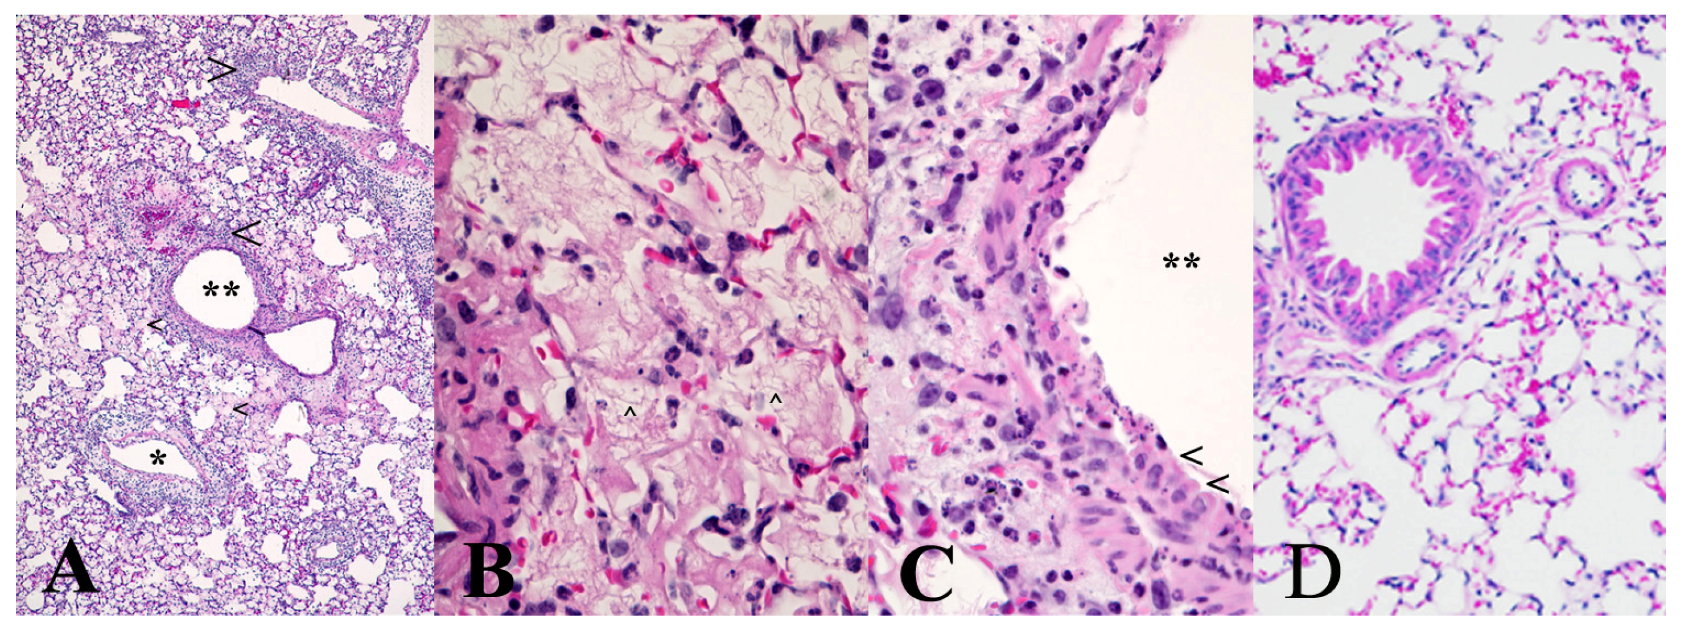

We carried out a limited histopathology study on the lungs of mice challenged intranasally with 10 μg/kg ricin to determine if the administered ricin reached the alveoli in this model. As shown in Figure 2, the pathological changes two days after challenge were patchy and characteristic of an acute inflammatory response similar to the changes observed in other inhalational models of ricin challenge [2,7,17]. Thus, the presence of proteinaceous material in the alveoli, perivascular and peribronchial edema, as well as cellular infiltration mostly composed of neutrophils into the lung tissue were all obvious and indicative of damage caused by ricin.

Figure 2. Mouse lung histopathology after intranasal ricin challenge. Ten female BALB/c mice were challenged intranasally with 10 μg/kg ricin, and on day 2, post-challenge mice were anesthetized and their lungs processed for histopathology. The panels above are representative photographs of the pathological changes in mice exposed to ricin. (A) Inflammatory cell infiltrates (large arrowheads) surround bronchi (**) and blood vessels (*), and many alveoli are filled with proteinaceous fluid (edema) evident as pink staining material (small arrowheads). Note also the presence of perivascular edema and hemorrhage affecting the vessel adjacent to the small bronchus; (B) Alveoli are largely filled by fibrin (arrowhead), and there are also some degenerate neutrophils and necrotic debris evident; (C) Only a limited region of the epithelium lining a bronchus remains viable (arrowheads); the remainder is necrotic. Note the edema of the peribronchial connective tissue and infiltration by neutrophils, many of which are degenerate. The pathological changes evident can be compared to the normal mouse lung histology shown in (D).